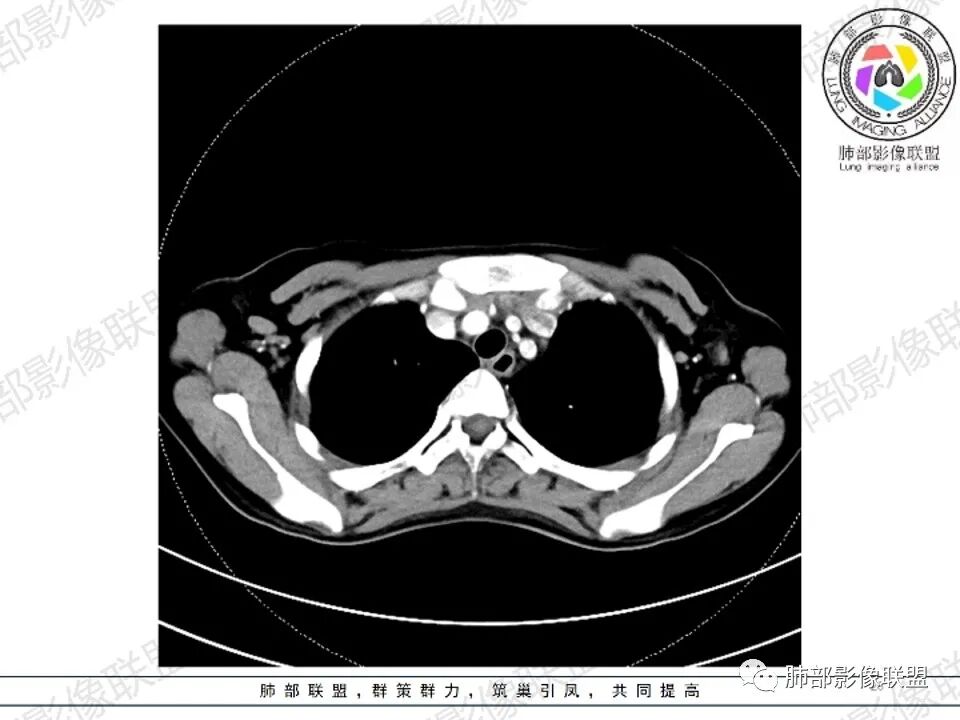

女,27,间断头晕、乏力3年,左眼视物模糊2月。贫血。胸部CT:前纵隔不规则肿块,多结节融合,边界不清,沿主动脉及肺动脉间隙生长,平扫密度欠均匀,增强扫描可见多发低密度坏死,纵隔血管供血穿行,腋窝多发大小不等淋巴结肿大。考虑恶性病变,胸腺癌?肉瘤?淋巴瘤?鉴别胸腺瘤、结节病等。

临床:年轻女性,慢性病程,多系统病变,头晕,贫血,视物模糊。

CT:定位纵膈病变,前中纵隔多发肿块,质软,塑形,密度不均匀,边界清楚。增强不均匀强化,坏死边界清楚,血管漂浮征。双侧腋下多组淋巴结肿大,明显异常强化。

2.影像显示前纵隔不规则块状影,依势贴附心脏大血管旁,密度不均,边界不甚清楚,有结节融合感。

3.病灶轻度不均匀强化,可见血管穿行,散在液性低密度区。

4.双侧腋窝区见增大淋巴结,边界清楚。

1.年轻女性,前纵隔不规则块状影,密度不均,边界不甚清楚,有结节融合感,轻度不均匀强化,可见血管穿行,最常见最符合的无疑是淋巴瘤!